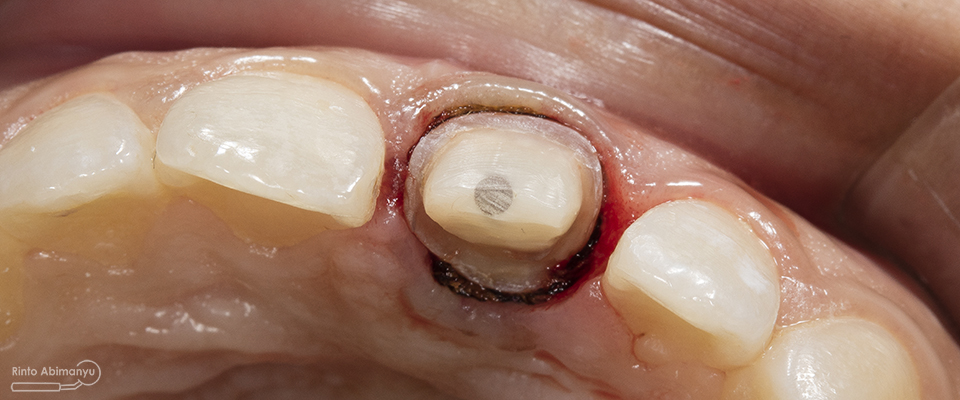

ini hasil preparasi gigi-giginya…

Hasil preparasi tampak depan

Hasil preparasi tampak oklusal